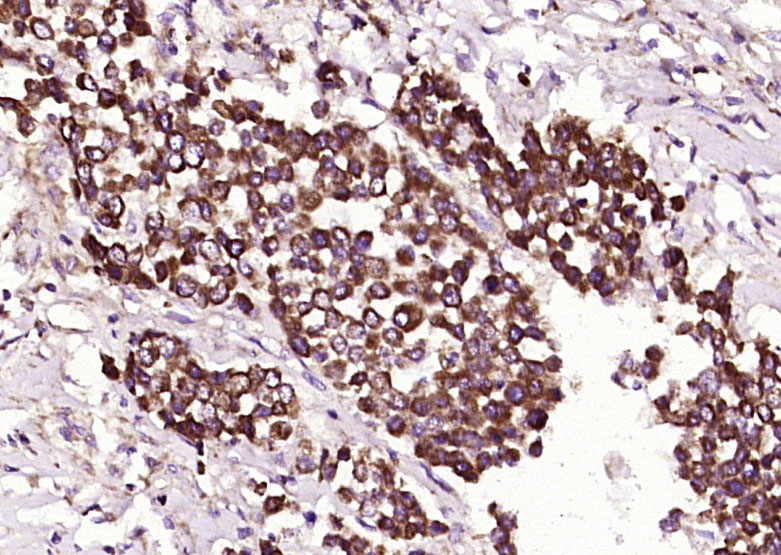

Paraformaldehyde-fixed, paraffin embedded (Human cervical carcinoma); Antigen retrieval by boiling in sodium citrate buffer (pH6.0) for 15min; Block endogenous peroxidase by 3% hydrogen peroxide for 20 minutes; Blocking buffer (normal goat serum) at 37°C for 30min; Antibody incubation with (Phospho-BRCA1(Ser988)) Polyclonal Antibody, Unconjugated (bs-8444R) at 1:400 overnight at 4°C, followed by operating according to SP Kit(Rabbit) (sp-0023) instructionsand DAB staining.